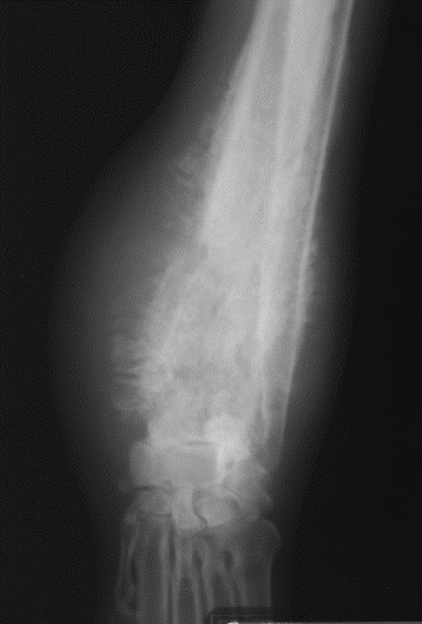

hypertrophic osteopathy signalment

middle to older dog

secondary to thoracic or abdominal dz/mass

spares small bones of carpus and tarsus

starts from MC/MT bones and goes up the leg symmetrically and bilateral

NO lysis but LOTs of periosteal rxn

AGG lesion

Hypertrophic Osteopathy